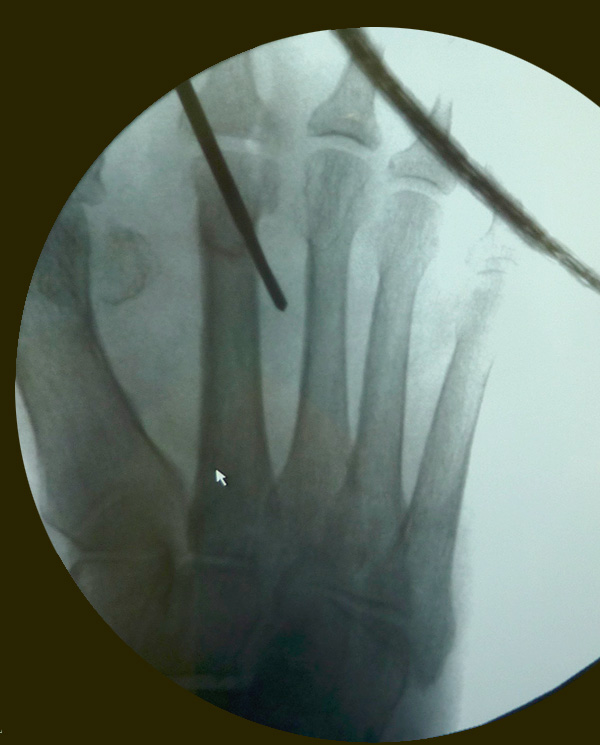

• Röntgenaufnahmen des Fuß in drei Ebenen im Stehen (siehe Abb. 2).

Zum Lesen der Bildbeschreibung und zur Vollansicht bitte das Bild anklicken. Bild: M. Walther.